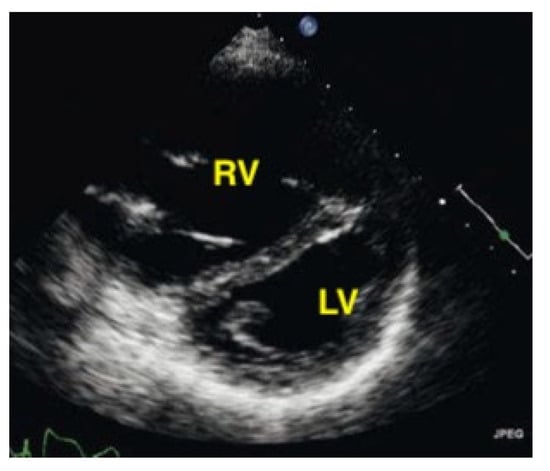

A pulmonary embolism large enough to compromise circulation is typically seen in more centrally located pulmonary arteries, and the subsequent pressure overload results in an enlarged right ventricle. Normally, the right ventricle is slightly smaller than the left ventricle. The size of the right ventricle compared to the left ventricle is best estimated in the apical four-chamber view with a sector probe. However, the subcostal four-chamber view will also reveal an unusually easily seen right ventricle when dilation is present and should be an indication to investigate further. In the case of a central pulmonary embolism, the interventricular septum is typically flattened (apical four-chamber view) and shows a D-sign (parasternal short-axis view) [,] (Figure 15, Figure 16 and Figure 17).

Figure 15.

The right ventricle is much bigger than the left ventricle.

Figure 16.

Parasternal short-axis view. The pathologically increased right ventricular pressure pushes the septum to the left side during diastole, so that a D-shape of the left ventricle results (RV = right ventricle, LV = left ventricle).